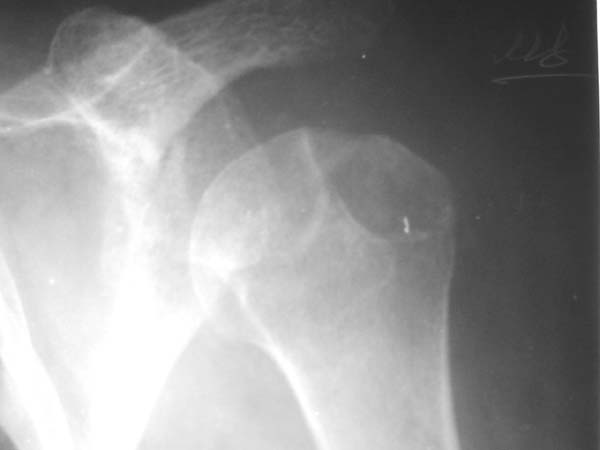

Re: Вывих плеча

> Непонятный очаг по заднему контуру

> Именно этот участок и смущает больше всего.

"Прицельная" съемка малопонятного очага.